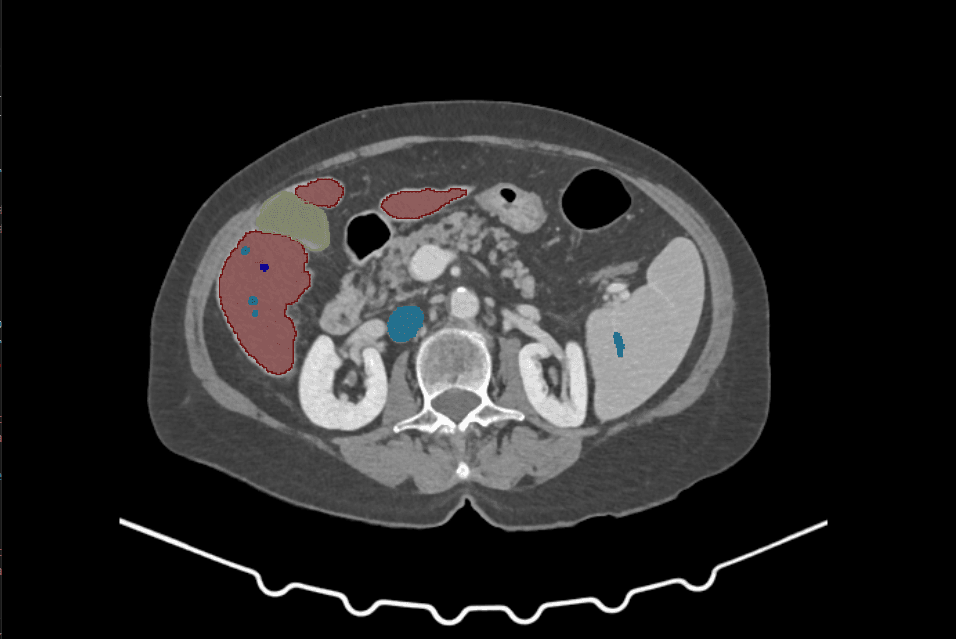

Una breve serie di slice provenienti da un caso segmentato automaticamente da ViC: scorri per vedere come le nostre reti segmentano organi, vasi e masse.

IntusAI addestra le reti ViC su un dataset multicentrico con oltre 2.600 TAC addominali e toraciche annotate. L'alta qualità delle immagini garantisce risultati affidabili in termini di segmentazione, visualizzazione e supporto decisionale nei flussi chirurgici.

I nostri modelli di segmentazione si basano su immagini ad alta qualità e grandi volumi di dati. Questo approccio rende ViC una piattaforma affidabile per AI training, radiomica e validazione clinica.